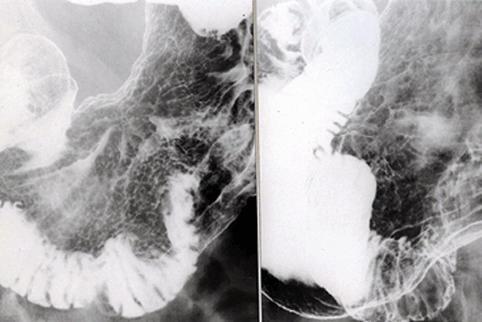

疾病(病理主体)的分类恶性上皮性肿瘤/腺癌

部位(按器官分)胃(部位)/胃角

检查方法X线

肿瘤的肉眼分类0型(表在型)/IIc型(IIc)

肿瘤最大直径40以上

肿瘤的深度m